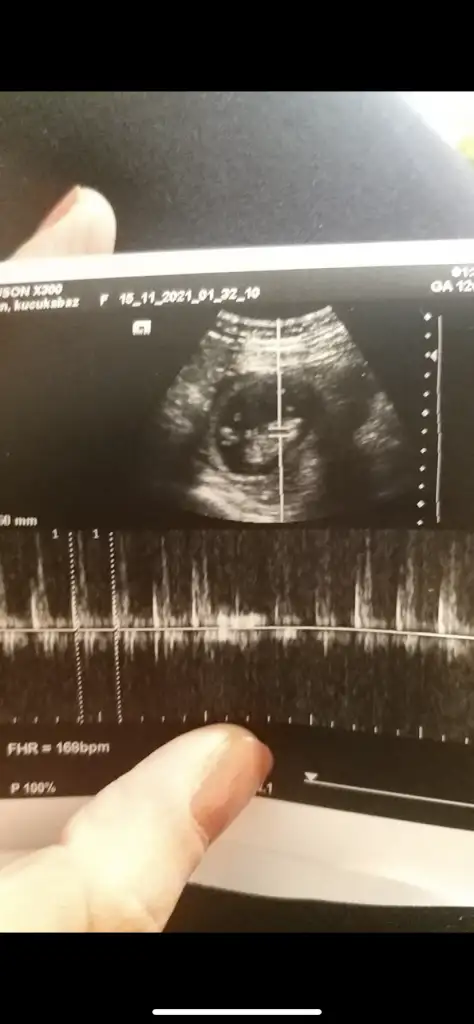

Bu haftalarda nub olmaz cnm 11 12 13 haftalar olmalı şekli kıza benzetimMerhabalar herkes sizi öneriyor bana da bir tanminde bulunur musunuz tam 14 haftalık ama kordon girdiği için emin olmamakla beraber erkek dendi içimden hep kız geçiyor rüya test vs ile cuma kesinleşecek ama sizden tahmin etmenizi istiyorum yardımcı olur musunuz

Bana sanki erkek demistin, doktorumuz 12.haftada %75 kiz demisti. Ama senin tahminin tuttu. Bence bi danismanlik merkezi ac baya baya tutuyormus senin tahminler.Emin olmadım sanki erkek gibi

Canım 12+6 bu ultrason bakarsın cook sevinirim10 hafta uygun değil şimdilik kız yönünde ama en iyi 11 12 13 haftalar olmalı

Ayy Dr yanılmışDoktor %70 kiz gibi ama daha erken onumuzdeki ay net belli olur dedi. Fakat prof dr oldugu icin yanilacagini sanmiyorum. Senin dr baya namini duydum sitede. Sen de emin olamamissin o zaman kız mi geliyor acaba